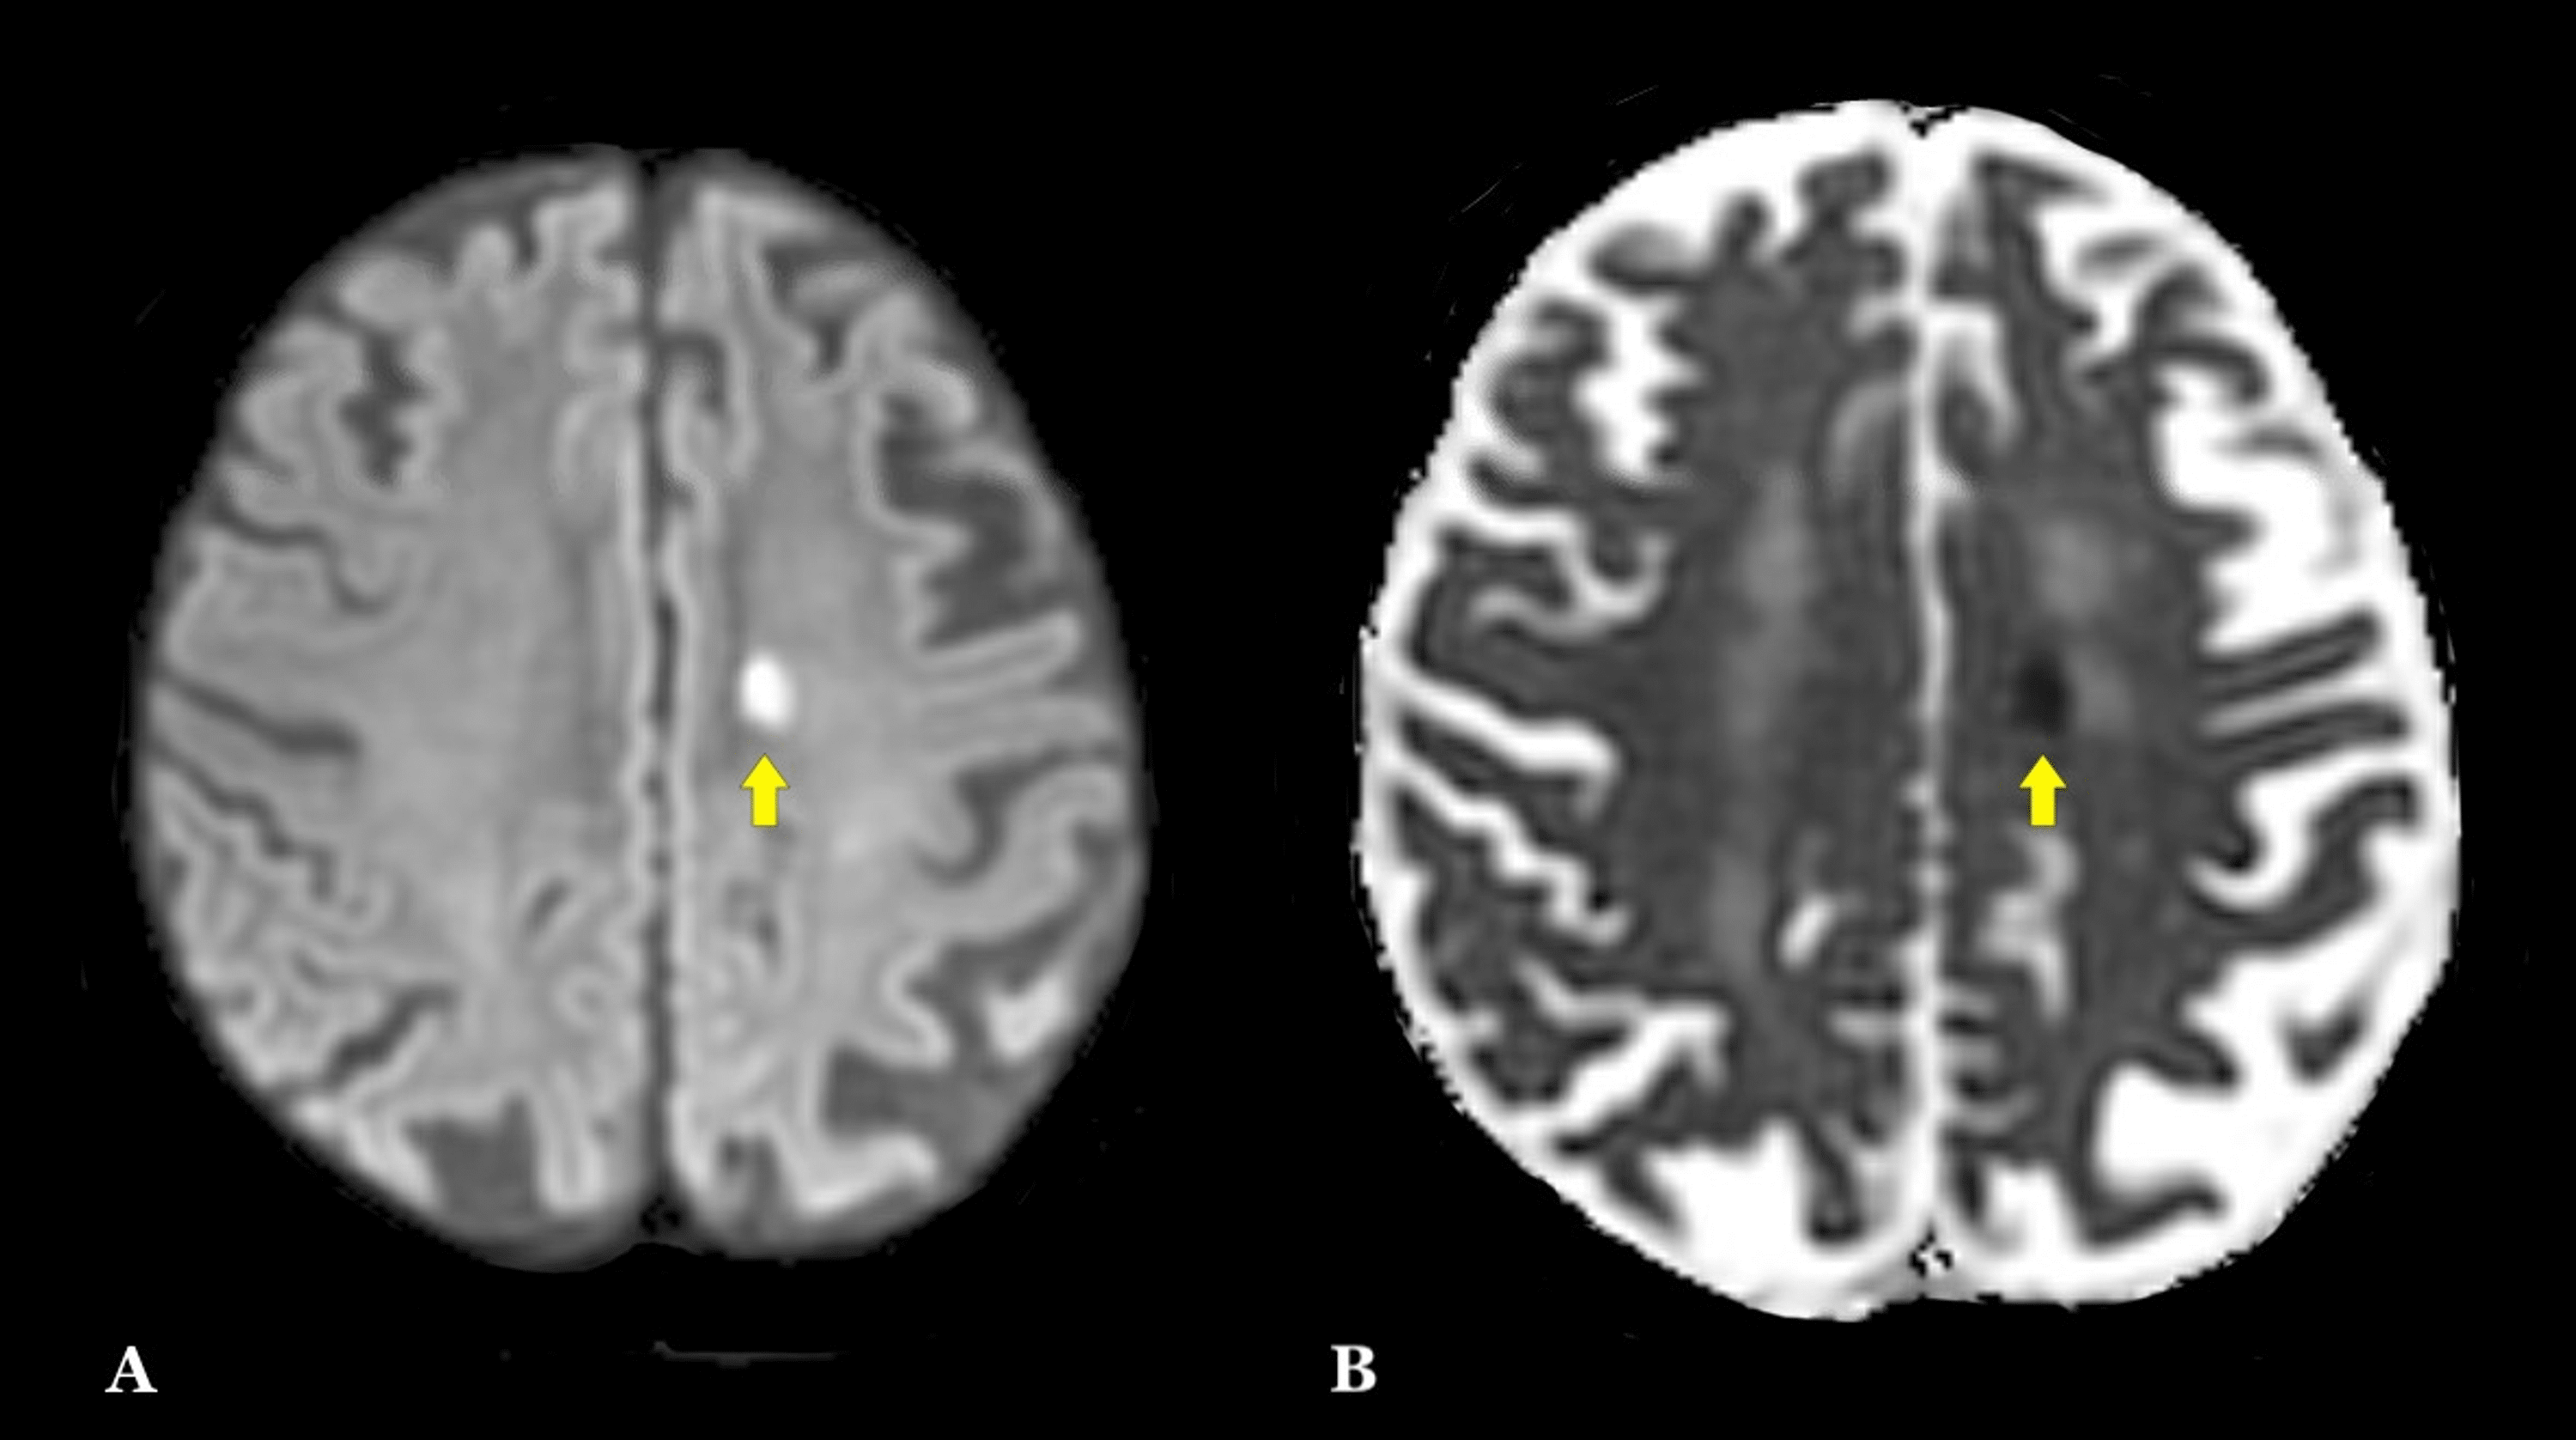

From www.cureus.com

Cureus Music to the Ears An Unusual Case of Frontal Lobe Stroke With Music Sequence Mri Mrf‐music sequence provides significant improvement in patient comfort compared with the mrf scan and other fast. It is also a fast and accurate quantitative method that quantifies multiple relaxation parameters simultaneously. A sagittal mri sequence is shown, which shows significant neural activity in the right anterior cingulate cortex (ba 24), left anterior cingulate. In order to examine what specific roles. Music Sequence Mri.